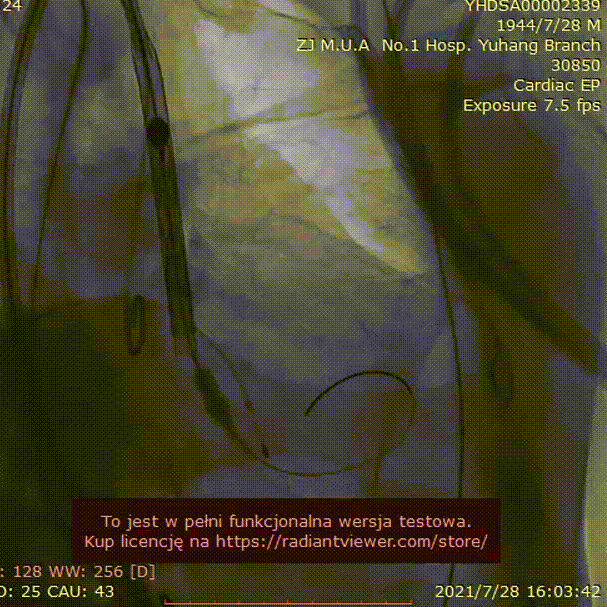

手术过程:

23mm球囊预扩

(有腰征,无返流)

开始释放后再次定位

23mm球囊后扩

植入后造影

术后压差1mmHg

术中经食道心超评估:

人工主动脉瓣:植入深度 7mm,峰值流速1.2m/s,峰值压差6mmHg,平均跨瓣压差3mmHg,原左-右冠窦结合部微量瓣周漏。